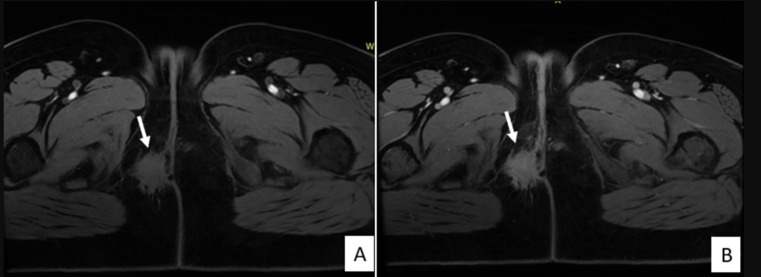

子宫内膜异位症是一种慢性非癌性妇科疾病,通常见于育龄妇女。它描述了子宫内膜腔外存在功能性子宫内膜成分、腺体和间质,最常涉及卵巢、腹膜和子宫韧带等盆腔结构。会阴子宫内膜异位症是一种罕见的盆腔外子宫内膜异位症,估计发病率在0.3%至1%之间。我们报告了一例36岁的孕妇,妊娠1段(G1P1),有阴道分娩史,没有子宫内膜异位症的病史,在接受会阴中外侧切开术两年后,出现了位于右侧会阴疤痕的疼痛肿块。肿块与周期性疼痛和生活质量明显受损有关。临床检查,结合超声和磁共振成像(MRI),建议在没有其他子宫内膜异位症病变的情况下诊断会阴子宫内膜异位症。由于患者拒绝手术,开始激素治疗,在8个月的随访中症状明显改善。虽然没有获得组织学证实,但典型的临床表现,令人回味的MRI特征以及对激素治疗的良好反应支持会阴子宫内膜异位症的诊断。在会阴切开术后出现周期性会阴疼痛的育龄妇女中,应系统地考虑这一未被充分认识的实体。

Endometriosis is a chronic, non-cancerous gynecological disorder that is typically observed in women of fertile age. It describes the presence of functional endometrial components, glands and stroma outside the endometrial cavity, most often involving pelvic structures such as the ovaries, peritoneum, and uterine ligaments. Perineal endometriosis is a rare form of extrapelvic endometriosis, with an estimated incidence of between 0.3% and 1%. We report the case of a 36-year-old woman, gravida 1 para 1(G1P1), with a history of vaginal delivery and no known history of endometriosis, who presented with a painful mass located on the right perineal scar two years after undergoing a mediolateral episiotomy. The mass was associated with cyclical pain and significantly impaired quality of life. Clinical examination, combined with ultrasound and Magnetic Resonance Imaging (MRI), suggested the diagnosis of perineal endometriosis in the absence of other endometriotic lesions. As the patient declined surgery, hormonal therapy was initiated, resulting in marked symptom improvement at 8-month follow-up. Although histological confirmation was not obtained, the typical clinical presentation, evocative MRI features, and favorable response to hormonal therapy supported the diagnosis of perineal endometriosis. This under-recognized entity should be systematically considered in women of reproductive age presenting with cyclical perineal pain following episiotomy.